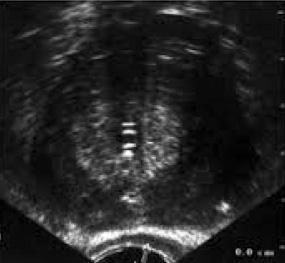

Valoración de la próstata vía transrectal:

- Se utiliza un trasductor de frecuencia media entre 8-10 Mhz.

- Se coloca al paciente en decúbito lateral izquierdo.

- Suele usarse un lubricante con anestésico.

El abordaje se realizará primero en escala de grises y posteriormente con Doppler para valorar la vascularización de la glándula.

Permite el diagnóstico de patologías como la hiperplasia benigna de próstata, prostatitis, quistes prostáticos, el cáncer de próstata.

Se utiliza como guía para la biopsia prostática.